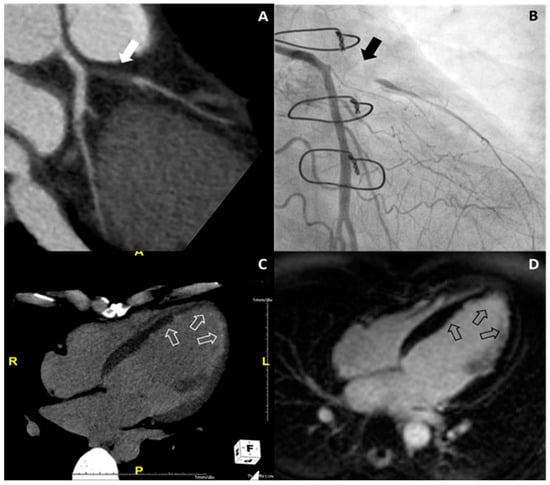

Details of the results from clinical follow-up are described in the Supplemental materials. Of 18 patients with ischemic HF from cardiac CT, 16 patients underwent CAG and significant CAD was confirmed. In Group II, two patients refused to undergo CAG and were diagnosed as ischemic HF based on CMR findings with myocardial infarction. One representative case of ischemic HF is shown in Figure 4.

Figure 4. Representative case of ischemic heart failure. On coronary CT angiography (A), total occlusion of the proximal left anterior descending artery (white arrow) is noted, and this finding was confirmed on conventional coronary angiography (black arrow) (B). On delayed-enhanced dual-energy CT with the four-chamber plane (C), subendocardial delayed enhancement is noted on the apical left ventricle and septal wall of the mid left ventricle (white open arrows), which was confirmed on cardiac MR (black open arrows) (D).